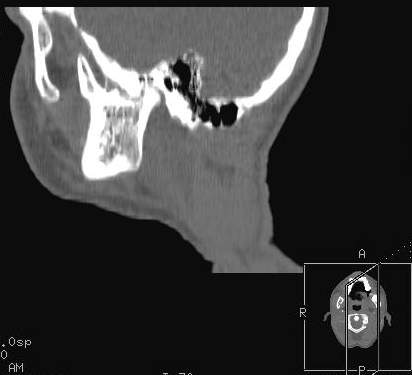

Пациент В., 13 лет. Диагноз: Костный анкилоз левого височно-нижнечелюстного сустава (ВНЧС), левосторонняя микрогения. Болеет с 2-х летнего возраста. Возможная причина развития анкилоза – воспалительный процесс (в первые 1,5 года жизни часто болел простудными заболеваниями, травму родители отрицают). В 3 и 5 лет проводилась редрессация – безуспешно.Прилагаются: ортопантомограмма, кадры СКТ с 3Д реконструкцией. Вопросы: определение тактики лечения – вид и сроки реконструктивно-пластической операции (этапов операции), а именно – неоартропластики и устранения микрогении, медикаментозная терапия в до- и послеоперационный период, ортодонтическое лечение.

Возможно проведение традиционной остеотомии с введением дермо-жирового трансплантата в линию остеотомии. Сроки ортодонтического лечения необходимо обсуждать совместно с ортодонтом и планировать начало лечения до и после оперативного вмешательства. Не исключено применение в дальнейшем остеотомии убоальвеолярных отростков с целью коррекции прикуса.

Мнение, высказанное специалистами из Питера, совпадает с нашим мнением и на следующей неделе мы планируем проведение указанного оперативного вмешательства (1-ый этап лечения). Если кому-то интересно, напишите мне на личный e-mail, представлю дальнейшие материалы по данному случаю.